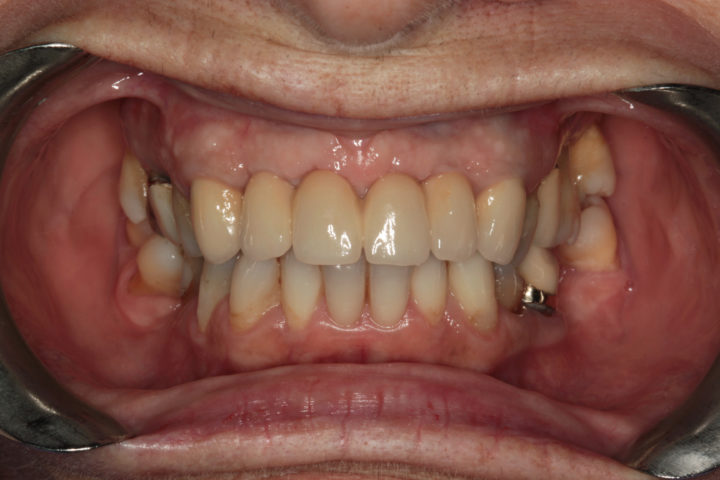

Risultato frontale:

Dopo l’intervento di implantologia, il nuovo incisivo su impianto si integra perfettamente per forma, colore e funzione. Il sorriso risulta naturale, armonico e completamente riabilitato.